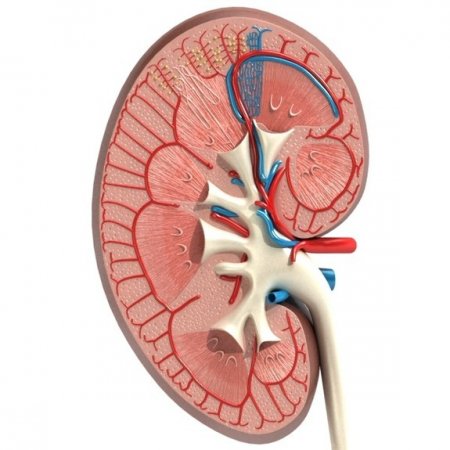

Böbreğin temel fonksiyonlarından birisi idrar üretmektir. Her 2 böbrekte idrar üretimine yol açan yaklaşık 2 milyon küçük ünite (nefron) vardır. Bir nefron temel olarak 2 kısımdan oluşur.

1.Böbreğe gelen kanın süzüldüğü filtre (glomerül)

2.Süzülen kanın idrara dönüştüğü uzun, yer yer kıvrımlı borular (tübül)